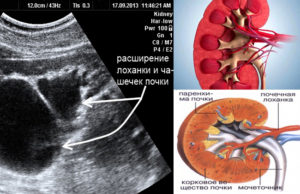

- УЗИ позволяет оценить форму и размер лоханок, чашечки, локализацию почечных структур, расположение вен. Исследование является безопасным для грудничков и выявляет патологию почек в утробе.

- 1 этап — пиелоэктазия. Характеризуется умеренным изменением размеров почки, что не оказывает негативное влияние на функционирование органа. Нарушений фильтрации и кровообращения не отмечается. Данный вид патологии диагностируется случайно на плановом ультразвуковом исследовании плода на 16-20 неделях беременности. После рождения врожденная патология у грудничка может быть обнаружена на плановом УЗИ брюшной полости в первый месяц жизни.

Во время обследования доктор видит состояние и размеры мочевыводящих путей на мониторе. Повод для беспокойства есть в том случае, когда УЗИ показало следующие нарушения:

- размеры лоханки почки увеличены до 10 миллиметров и более;

- границы мочеточника с пораженной стороны также расширены;

- проявляется недостаточность работы почек, вызванная снижением функции данных органов;

- выявлены камни и новообразования в мочевыводящем тракте;

- на протяжении 1 года жизни лоханка расширяется достаточно быстро;

- имеются некоторые отклонения в развитии и строении мочеточников или почек.